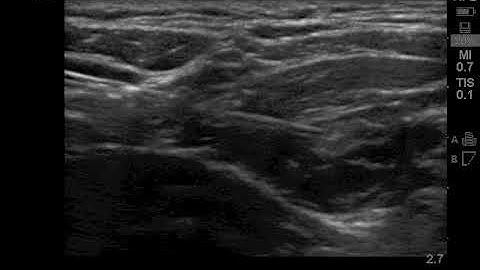

Superior Trunk Block - Appropriate LA Spread ("Block Bytes")